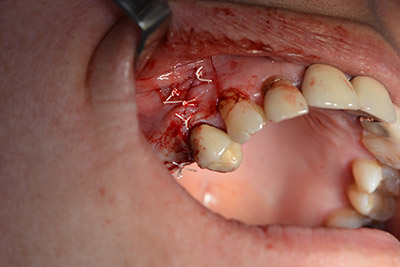

Acto seguido, se coloca el implante y se estructura el hueso. Dado el tamaño del aumento, en el caso que nos ocupa se utilizó hueso autógeno, que había surgido como virutas de fresado en el implante 16 y en la fenestración 14 y se había recogido con un colector óseo, y se combinó con material de reemplazo óseo.

Una membrana reabsorbible formó la barrera en sentido bucal y cubrió el aumento. Por último se procedió a la sutura de modo que no penetrara saliva (figuras 15 a 19).

cierre de la herida para que no penetre saliva

Imagen 19